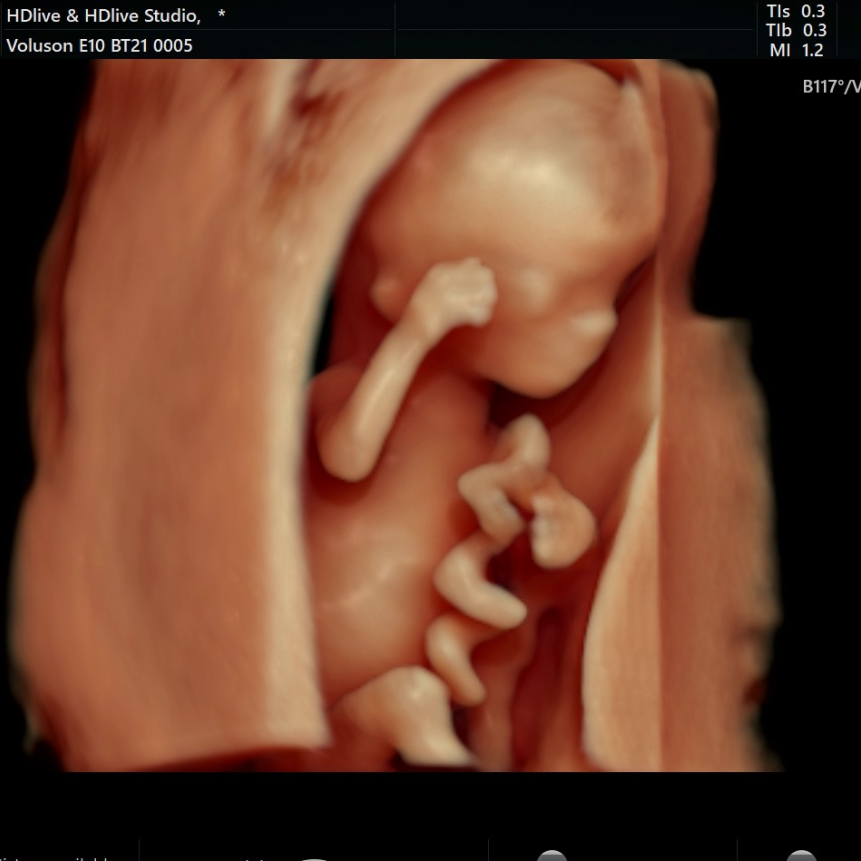

二、高清画质,成像效果惊人

相较普通四维彩超,E10的高清画质堪比IMAX电影大片!

过去的四维彩超能看到宝宝吐舌头、吃手指,但常常看到胎宝宝就像个“小泥人”,只能看看大致轮廓;E10四维彩超,可以实现您与宝宝的超高清“隔空对视”,直接观察他们的一举一动、乖巧秀容,包括:皱眉、微笑、打哈欠、吸吮等,提前享受将为人父人母的喜悦。